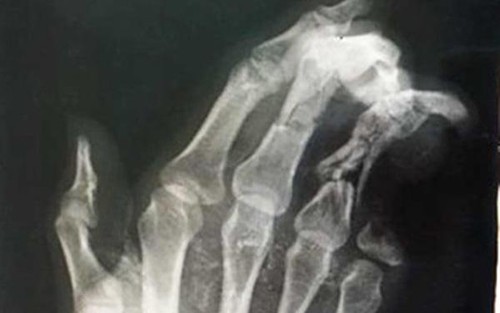

X-射線顯示傷者左手小指斷失了2節。(圖源:院方提供)

據初步消息,昨日中午11時45分許,當梁清維在租賃住房內一邊使用手機一邊充電時,該手機突然爆破。事故導致他的左手掌嚴重損傷,又使尾指斷失兩節。後來,傷者在林同省第二全科醫院接受初步救治和傷處掃描,並獲送入手術室縫合傷口。林同省第二全科醫院領導表示,傷者的斷失兩節尾指無法進行移植手術復原。這是給邊用手機邊充電習慣者的一次嚴厲警示◆